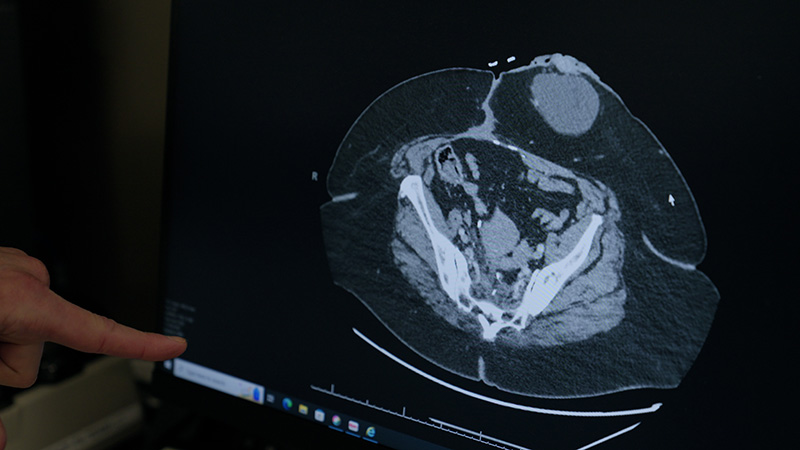

Effective colorectal cancer care begins with an accurate diagnosis. At Henry Ford Health, we offer the latest tests and procedures, so you receive the answers you need promptly. After a colorectal cancer diagnosis, our experts work together to select the best treatments for you.

We may use several tests to diagnose colorectal cancer:

Staging is the process of finding out if and how far cancer has spread (metastasized). This information is important for diagnosing colorectal cancer and determining the most effective treatments.